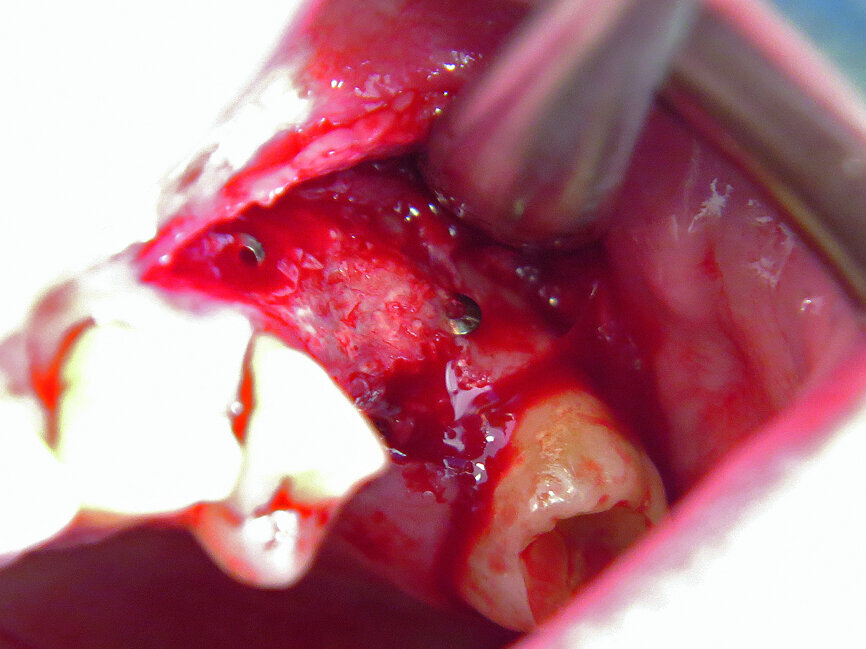

Fig. 2: Micro-osteoperforation in order to enhance bone formation.

The first was a 51-year-old patient who smoked 30 cigarettes per day and suffered from diabetes and stress (Figs. 1–8). The second was a 76-year-old male patient in good physical condition who smoked 40 cigarettes per day. He underwent reconstruction of the premaxilla (Figs. 9–13). The third was a healthy female patient of 24 years of age who smoked 20 cigarettes per day. She required a sinus lift in region #25 (Figs. 14–21). The patients were informed of the intended process in detail and signed the surgical protocol containing information concerning possible risks of failure and complications, as well as information on the alloplastic and synthetic materials to be used.